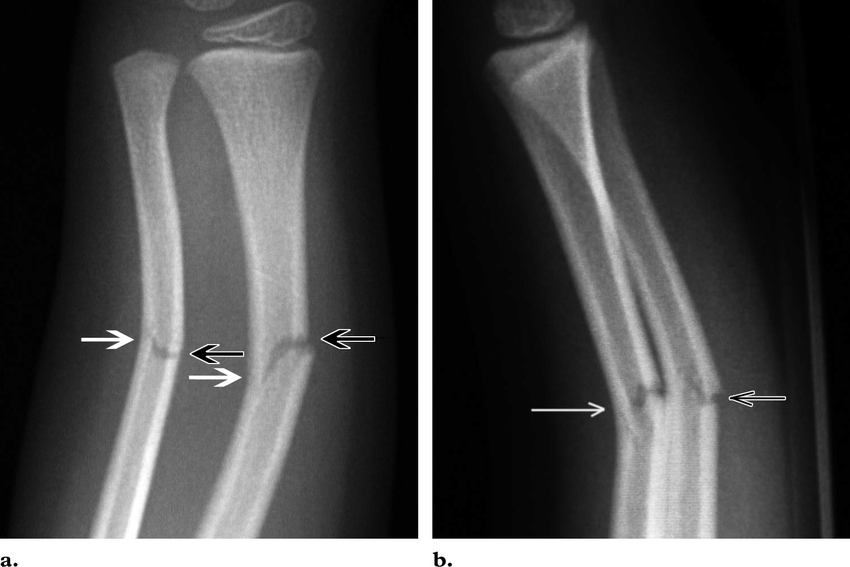

Greenstick Fracture - एका बाजूने फ्रॅक्चर, पण हाड वाकल्याने ते पूर्ण न तुटणे. हे फ्रॅक्चर लहान मुलांमध्ये जास्त आढळून येते कारण त्यांची हाडे लवचिक असतात.